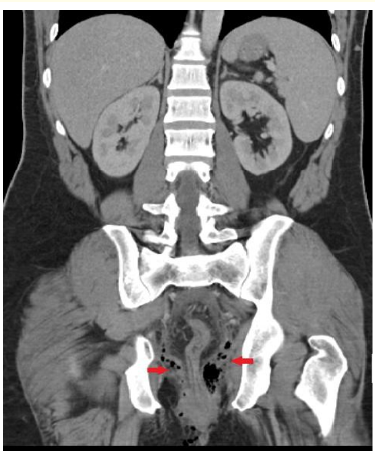

Seminal Vesicular Cyst: About 2 Case Report

Nizar Cherni, Abdallah Chaachou, Wael Ferjaoui*, Samir Ghozzi and Mohamed Dridi. 6(4): 85-87.